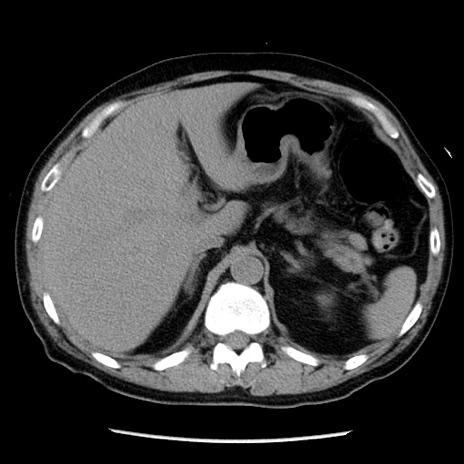

症例29(横断像)

【症例】40歳代男性

【現病歴】2日前から胃痛あり。徐々に周期的な激痛に変化した。本日になっても激痛があるため受診。

【身体所見】意識清明、BT 38-39℃台あり、腹部:膨満、やや硬、右下腹部に圧痛あり。

【データ】WBC 8500、CRP 23.26